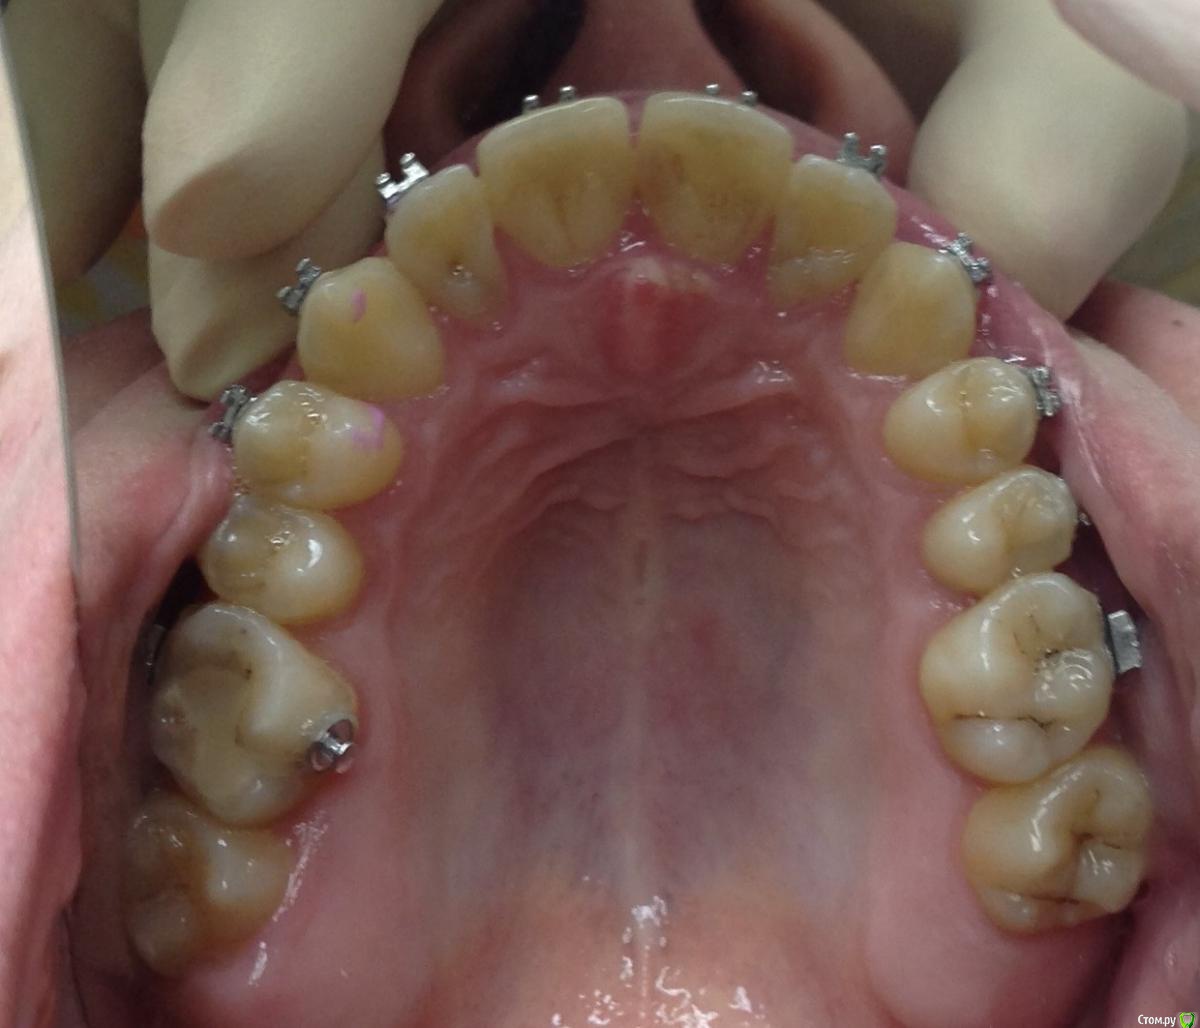

KoroNa Опубликовано 13 января, 2015 Поделиться Опубликовано 13 января, 2015 Здравствуйте. Опыт у меня совсем небольшой, можно даже сказать никакой на данном этапе. Пациент достался "по наследству" от подруги. Приехал учиться в наш город, она и пристроила мне. Я делала свое дело, меняла лигатурки, зная, что пациент периодически ездит в свой город и будет контроль лечения со стороны моей коллеги. А та, не долго думая, в декрет укатила с двойней. Когда увидела пациента, то как РАДА НЕ БЫЛА - ничего не сказать.3класс. вертикальный тип роста. Явные признаки к комплексному орто\хир лечению. Но она взялась, пожалела\попросили.....удалила премоляры на н\ч и начала дистализацию. Никаких ТРГ и моднлей в помине нет, да и я еще когда брала его даже фотографии не делала.Не хочу на форуме ругаться, но пациент "какашка" .......гигиенты нет как в полости рта, так и на лице...пропуски приемов....и т.д.НО! Подруге пообещала....Я сразу написала, что опыта ноль, только благодаря нашим лекторам стала сейчас обращать внимание на симметрию, на сустав и т.д. И вот, заходит пациент, на очередную смену лигатур, такой красивый в кабинет и что я вижу.....нижняя челюсть смещена влево, явная асимметрия. Куда мои глаза и мозги смотрели. Очень прошу помочь мне советами, что сейчас нужно сделать, с чего начать Ссылка на комментарий

KoroNa Опубликовано 20 января, 2015 Автор Поделиться Опубликовано 20 января, 2015 Думаю паниковать пока рано. Такое иногда бывает при значительном перемещении зуба/зубов, когда возникают контакты бугор-в-бугор, а н.ч отвечает компенсаторным смещением в ту или иную стогону. Если ЦЛ н.ч при максимальном оркрывании рта мигрирует, то всеОК. В любом случае проведите полную диагностику, а ОПТГ сейчас сделайте в положении ЦО (при полном/максимальном смыкании зубов). Это даст возможность оценить симметрию СГ.PS с какой целью стоит лингвальная кнопка на в.ч, носит ли пациент эластики и если да то как?Здравствуйте.Центральная линия при максимальном открывании рта практически "централизуется", но там есть еще и смещение ЦЛ из-за миграции резцов влево."ОПТГ сейчас сделайте в положении ЦО (при полном/максимальном смыкании зубов" - т.е. объяснить пациенту чтобы сомкнул рот на все зубы как смыкает обычно? не нужно смещать челюсть и делать прикусной шаблон?Кнопка справа на 6ом моляре применялась для устранения перекрестной окклюзии. пациент оторвал замок и около месяца не появлялся на прием. вот зуб и уехал. Ссылка на комментарий

KoroNa Опубликовано 23 января, 2015 Автор Поделиться Опубликовано 23 января, 2015 Кнопка справа на 6ом моляре применялась для устранения перекрестной окклюзии. пациент оторвал замок и около месяца не появлялся на прием. вот зуб и уехал. Что значит "уехал" , а конкретнее куда?Спасибо за ваши комментарии. Зуб 1.6 "ушел" в небную сторону -палатиноокклюзия, если не ошибаюсь. Ссылка на комментарий